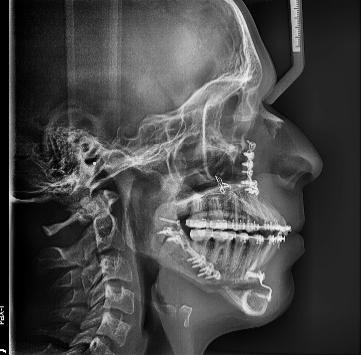

Figura 1. Perfil de inicio. Figura 2. Cefálica lateral.

Se presenta un paciente en edad de 15 años y 2 meses. Refiere que acude a consulta por evaluación. En la valoración extraoral presente la hiperdivergencia y sus posiciones dentales (Figura 1), tiene un perfil convexo con hiperactividad del músculo mentoniano e incompetencia labial, y en la radiografía lateral de cráneo inicial (Figura 2) se aprecia el patrón esquelético clase II severo.